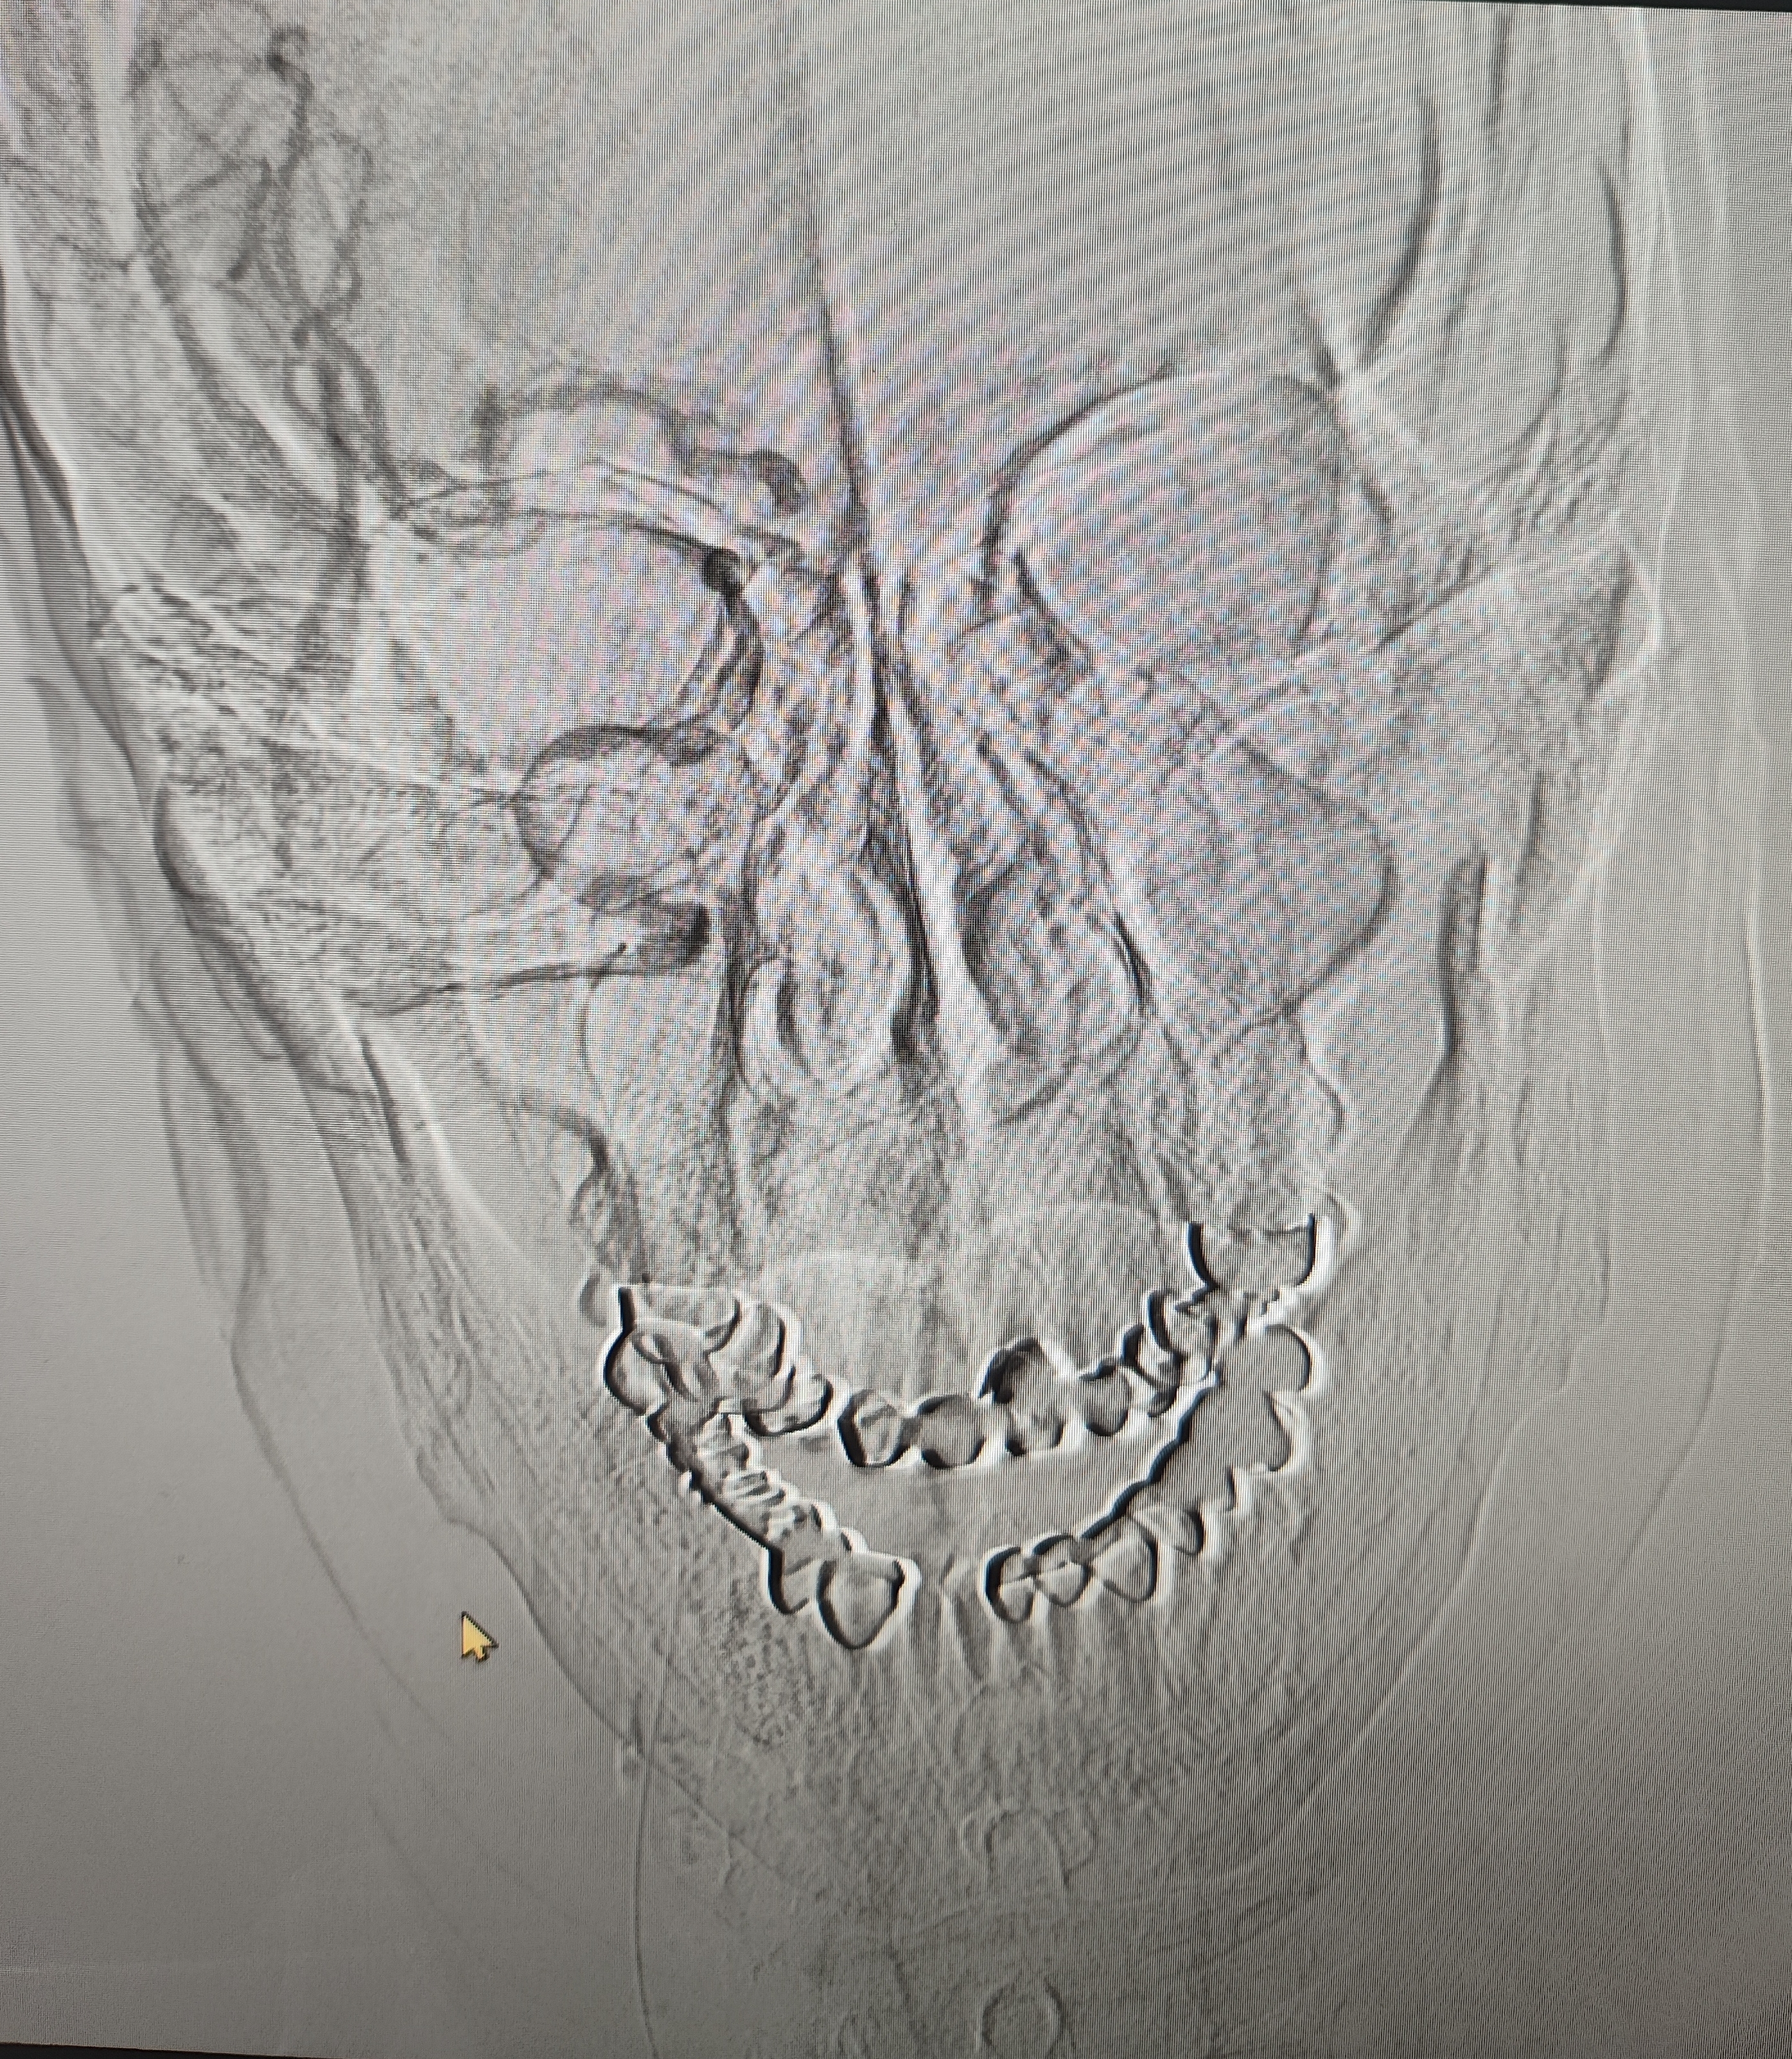

颈总巨大斑块急性闭塞的血管内治疗(双颈动脉支架桥接+支架释放后掉斑块,抽吸取栓)

84岁男性,既往右侧颈动脉狭窄病史8个月,多次脑梗未治疗,本次突发左侧肢体无力来诊,发病30小时后转入我院。

症状进行性加重,意识逐渐模糊,烦躁,左上肢肌力1级,左下肢肌力2级,当地考虑开通难度大,转入我院。

急诊上台。